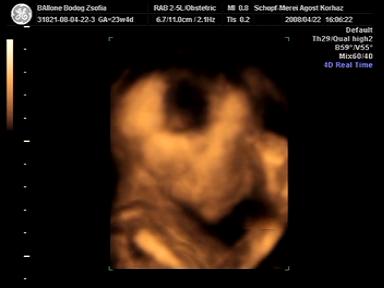

na, megvolt a 4D ultrahangunk tegnap! nagyon klassz volt, ugye abban megegyezhetünk, hogy szinte minden nap nézegetnénk a babánkat, babáinkat, szóval tényleg hatalmas élmény!

mindjárt teszek fel képeket is ;)

amúgy a bébi olyan 730 g körül van most, de ami a fura, hogy mostanában sosem mér hosszúságot! azt mondta a néni, hogy ilyenkor kb. 3-4 cm a talpa! :) annyira édes! tényleg olyan kis manócska!

a lelet grav.s. 24-et határoz meg, BPD 60mm, OFD 76mm, AC 198mm, és végül FL 46mm. sosem tudom, hogy mik ezek a betűk, de mindjárt utánanézek! ;)

szóval akkor a képecskék!

Kép Benedek 23 hetesen és 4 naposan Kép Benedek ásítás közben Kép és az igai bizonyíték, hogy kisfiú